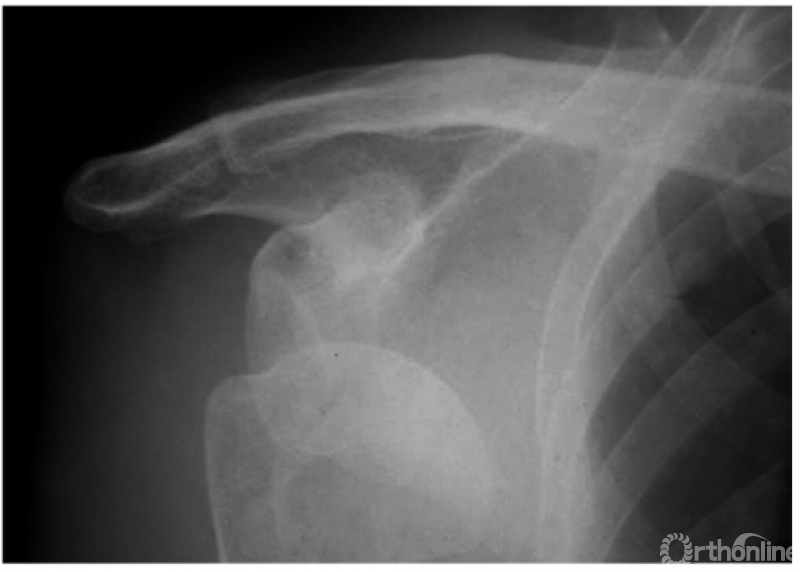

例1:肩关节盂下脱位(如下图)。